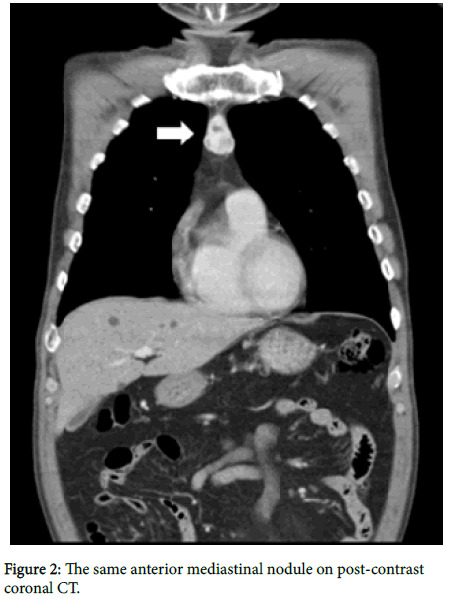

A 67-year old man presented with dysphagia for several weeks. Endoscopy was performed for suspected esophageal lesion, and an upper esophageal cancer was found and proved by biopsy. A contrast enhanced computed tomography (CT) was performed for cancer staging. Post-contrast CT demonstrated concentric esophageal wall thickening which was compatible with the presence of esophageal cancer. Post-contrast CT also revealed an avidly and heterogeneously enhancing nodule in anterior mediastinum (arrows in Figures 1 and 2). This nodule demonstrated high attenuation on pre-contrast CT (arrow in Figure 3). The rest of the CT exam showed no remarkable findings.

Due to the possibility of this anterior mediastinal nodule being an anterior mediastinal tumor or atypical metastatic lymphadenopathy, surgical biopsy of the anterior mediastinal nodule was performed as well as esophagectomy. Esophageal cancer was confirmed by histopathologic findings. However, the surgical biopsy of the anterior mediastinal nodule revealed an ectopic thyroid with colloid follicles unexpectedly.